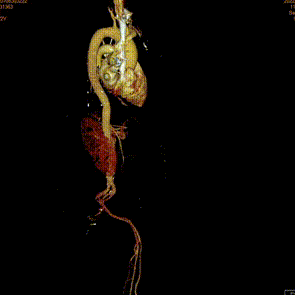

术后1w——冠脉CTA

● 术前应进行充分CT评估,摒弃唯冠脉高度论,需要结合窦部大小及高度、STJ大小、瓣叶的长度、瓣叶增厚和钙化分布情况等因素,综合考量冠脉风险。